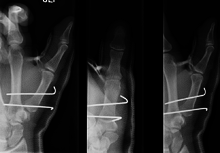

- For Bennett fractures where there is between 1 mm and 3 mm of displacement at the trapeziometacarpal joint, closed reduction and percutaneous pin fixation (CRPP) with Kirschner wires is often sufficient to ensure a satisfactory functional outcome. The wires are not employed to connect the two fracture fragments together, but rather to secure the first or second metacarpal to the trapezium.